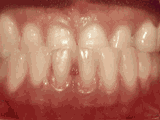

第四種---

牙列擁擠,牙槽骨過窄,牙齒沒有足夠空間,只好前后左右高低上下亂長,經(jīng)過矯正后的牙齒是這樣的~